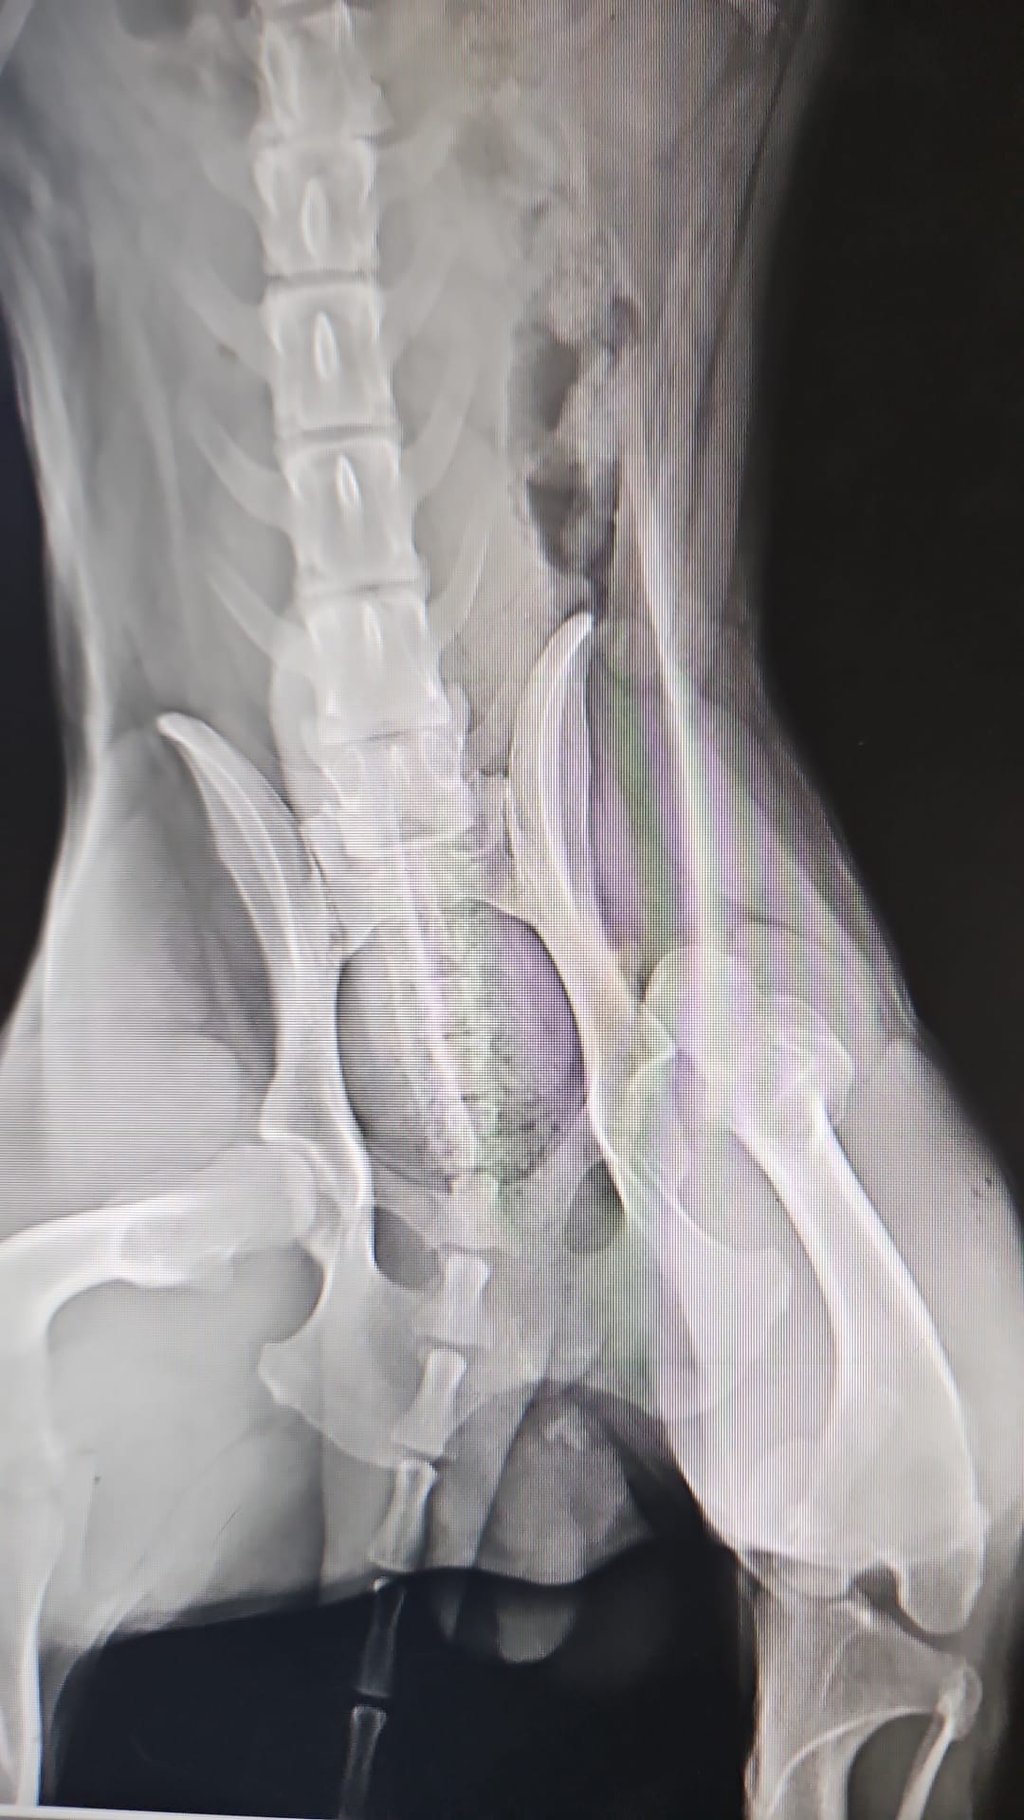

Bei der Operation wurde eine Femurkopfresektion (FHO) durchgeführt. Zeitgleich wurde Sebastian auch kastriert, sodass ihm ein weiterer Eingriff zu einem späteren Zeitpunkt erspart bleiben konnte.